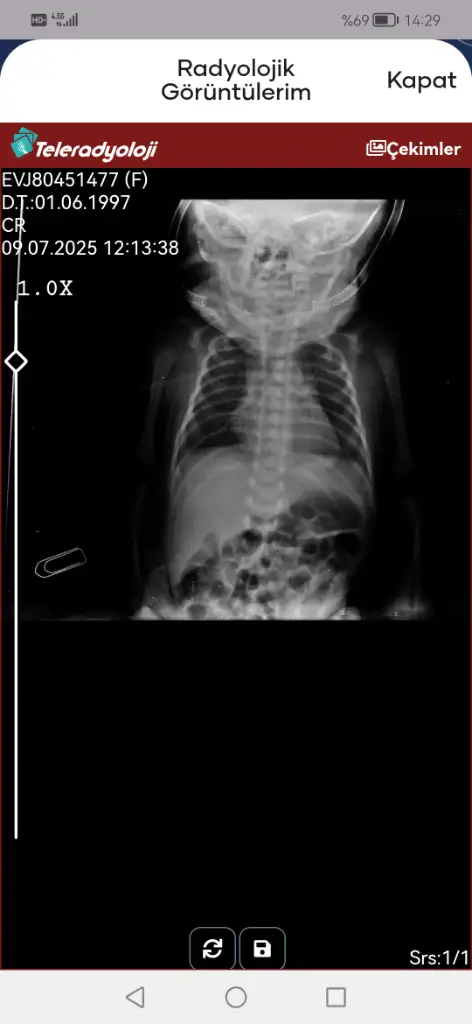

Evet entübasyon hortumu görünmüyor iki hortum olmalıydı ağzında. Entübeden ayrılması da iyi bir şey süt de azıcık gaz yapmış hatta bebişe. Süt aldıkça bu değerler toparlanır. Kan gazına göre bebeğiniz solunumu tölere edebiliyor diyebiliriz bunlar güzel haberler

• Screenshot_20250709_142908_tr.gov.saglik.enabiz.webp

Screenshot_20250709_142908_tr.gov.saglik.enabiz.webp

16,8 KB · Görüntüleme: 19